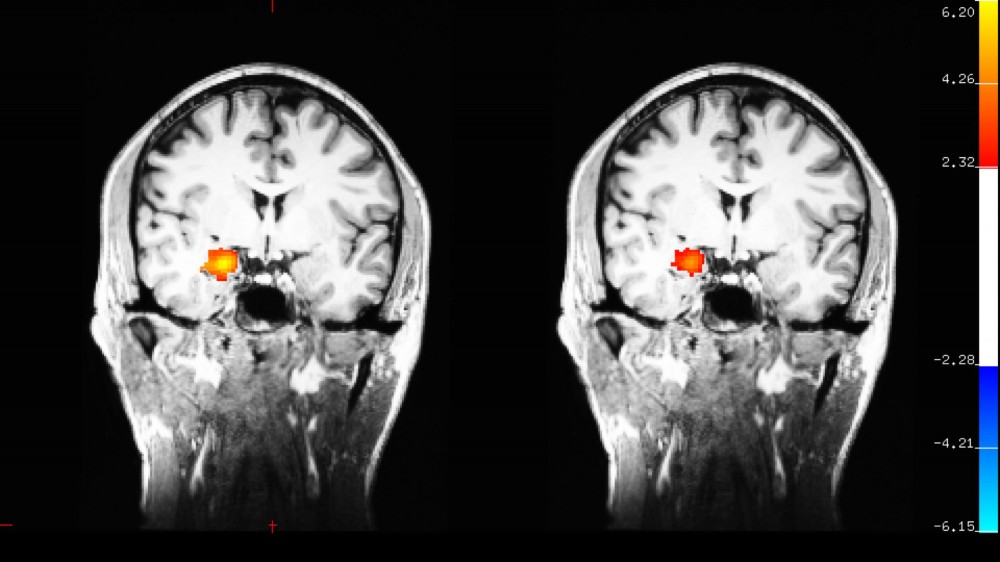

Desbordes使用功能性磁振成像(fMRI)作為研究方法,記錄下患有抑鬱症參加者腦部在接受以「認知治療」角度出發的靜觀訓練兩個月前後的變化。發現主要變化在杏仁體(amygdala),杏仁體在腦部中負責調節內臟功能和產生情緒功能。實驗給參加者看一些能挑起情緒的照片,左邊的是接受靜觀訓練前,右邊是接受訓練後,發現杏仁體活躍程度有所下降。